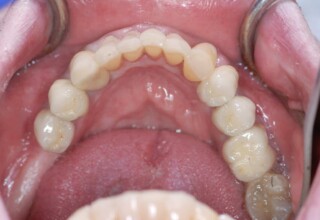

Εκτεταμένη αποκατάσταση με στεφάνες(θήκες) σχεδόν σε όλα τα δόντια λόγω εκτεταμένων αποτριβών, παλαιών αποκαταστάσεων, οπισθίων απονευρώσεων και αισθητικών προβλημάτων. Ο ασθενής(60 ετών) παρουσίαζε έντονο βρυγμό (τρίξιμο δοντιών) που δεν είχε αντιμετωπίσει ποτέ, με αποτέλεσμα μεγάλες αποτριβές που απειλούσαν την ακεραιότητα των οπισθίων δοντιών. Οι ανασυστάσεις(σφραγίσματα) των δοντιών έγιναν κυρίως με συγκολλούμενα ρητινώδη υλικά και τρεις χυτούς άξονες ψευδοκολοβώματα. Τοποθετήθηκαν προσωρινές στεφάνες όπου εκτιμήθηκε το επιθυμητό μέγεθος, το σχήμα και η θέση των δοντιών πριν κατασκευαστούν οι τελικές μόνιμες στεφάνες.